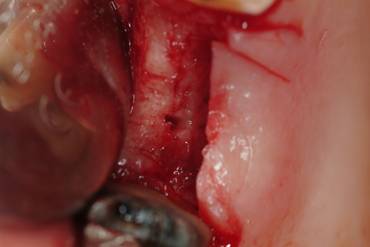

A buccal full thickness flap was harvested and the presence of a small OAF was verified. (Fig.3).

Figure 3

Flap elevation.

Int J Med Sci Image